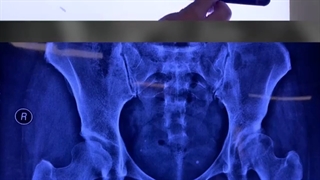

.نتیجه جراحی استوتومی گانز یا عمل اصلاحی در رفتگی مادرزادی ران در بیمار عزیزمون از تبریز

ممنون از اعتماد شما